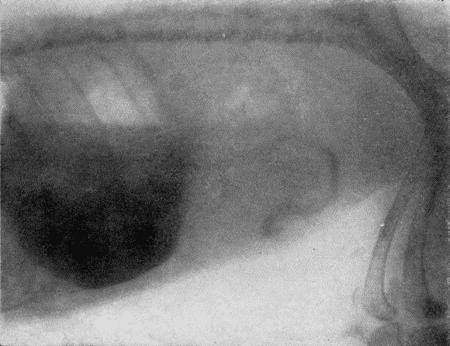

Накачивание воздуха в желудок производят под контролем на просвечивающем экране. В момент, когда баллон с воздухом полностью заполнит желудок и тень печени будет выделяться четко на очень светлом фоне растянутого желудка сзади и на светлом легочном поле спереди, дальнейшее нагнетание воздуха прекращают и вентиль груши закрывают (рис. 167).

Такой методикой исследования можно обнаружить увеличение печени, изменение конфигурации задней поверхности печени в результате целого ряда патологических процессов, опухоли печени и диафрагмы.